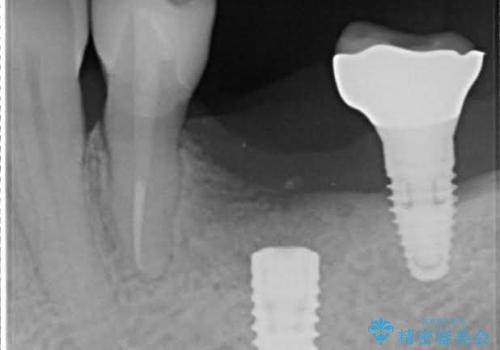

- 単独のインプラント補綴にて咬合の回復を計画した。

インプラントの種類:straumann SLActive

かぶせ物の種類:Bellezza screw retain